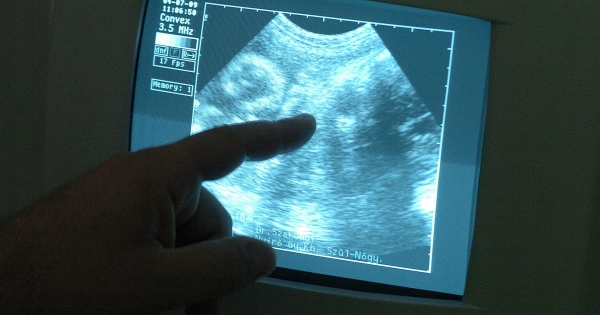

A termékenységi kezelések számának növekedésével a munkáltatóknak időszerű elmélyülniük az emberi reprodukciós eljárásokban részt vevő munkavállalók munkajogi védelmére vonatkozó szabályokban.